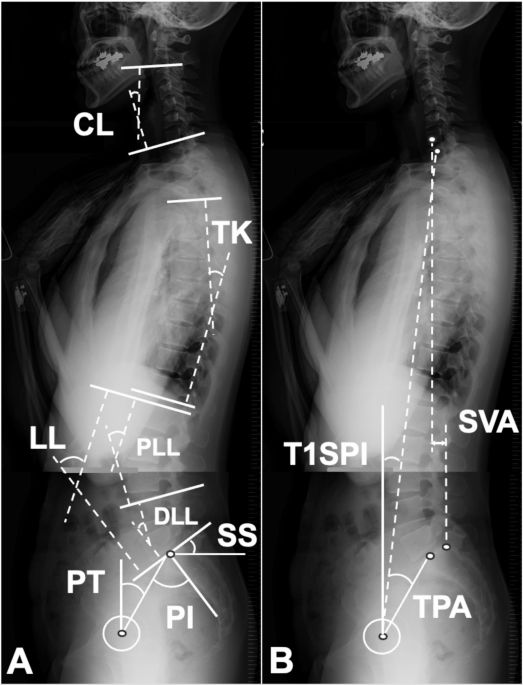

Spinal deformity surgeons must often deal with revisions. This is a 57yo F who presents with severe back pain and difficulty standing. Here are her spinopelvic parameters and imaging. She also has a pseudoarthrosis. What do you offer?